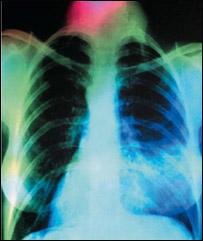

صحت و زندگی: سينه بغل

سينه بغل

سينه بغل يا نمونيا به التهاب شديد ريه ها يا شش ها گفته می شود.

البته از اثر اين بيماری، شش ها پر از چرک شده و رسيدن اکسيجن به خون با مشکل مواجه می شود.

درين بيماری بدن به کاهش اکسيجن دچار شده، ريه ها مملو از چرک و آب زرد رنگ می شوند .

شش ها کار اصلی خود را که اخذ اکسيجن است به درستی انجام داده نمی تواند و بدن به کاهش اکسيجن دچار می شود.